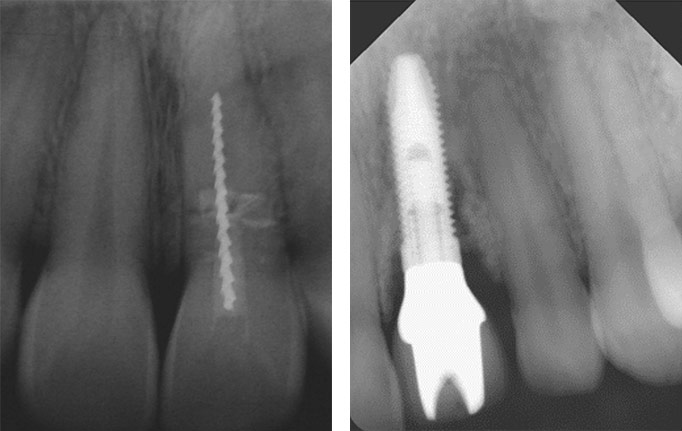

Zum Ausschluss von möglichen Folgeschäden sind regelmäßige Kontrolluntersuchungen nötig. Nach allen Arten von Frontzahntraumata müssen in regelmäßigen Abständen Vitalitätstest der betroffenen und der umliegenden Zähne erfolgen, am Unfalltag, nach 7 Tagen, nach 4 Wochen, nach drei Monaten, nach 6 Monaten und dann jährlich, um mögliche negative Folgen einer stillen Pulpennekrose wie Ankylose, internes Granulom oder externe Resorption rechtzeitig zu diagnostizieren. Die Anfertigung von Zahnfilmen zur Verlaufskontrolle ist frühestens 1-3 Monate nach dem Unfalltag indiziert und richtet sich nach dem jeweiligen Verletzungsmuster.

Röntgenuntersuchungen sind in der Schwangerschaft bei entsprechender Indikation und Schutzmaßnahmen durchaus erlaubt. Die Strahlenbelastung im Bauchbereich entspricht dabei noch nicht einmal der normalen täglichen Strahlenaufnahme.

Ein Beispiel: Eine Einzelzahnaufnahme entspricht einer effektiven Dosis von 1μS (Mikrosievert), die Strahlenbelastung einer modernen digitalen Panoramaaufnahme entspricht ca. 8μS. Zum Vergleich, ein Flug von Frankfurt nach New York und zurück führt zu einer durchschnittlichen effektiven Dosis von ca. 100 μS. Röntgenaufnahmen zur Absicherung der Diagnose sind also durchaus zu vertreten. Die letztendliche Einwilligung zur Röntgenuntersuchung muss aber durch die werdende Mutter gegeben werden. Bei vorhandenen Zweifeln, wenn es um Röntgen oder Medikationen geht, empfiehlt sich immer die Rücksprache mit dem Frauenarzt.

Die digitale Volumentomographie (DVT) ist ein dreidimensionales, bildgebendes Tomographie-Verfahren. Diese Technik ist ein computerunterstütztes Röntgenverfahren zur Erzeugung von Schichtbildern. Dabei wird unter Einsatz von Röntgenstrahlen ein dreidimensionales Bild der Kieferknochen erzeugt, ähnlich zur Computertomographie (CT). Im Gegensatz zum CT benötigt diese Technik aber nur einen Umlauf, da die Schichten mittels eines Strahlenkegels anstatt mit einem Strahlenfächer erzeugt werden. Dadurch hat ein DVT eine geringere Strahlenbelastung als ein CT-Volumen vergleichbarer Größe und ist deshalb für Zahnärzte und Oralchirurgen mit entsprechender Fachkunde für die Zahnmedizin zugelassen.

Indikationen für eine DVT Diagnostik in der Zahnheilkunde sind unter anderem die Implantatplanung, Planung umfangreicher Zahnfreilegungen oder riskanter Osteotomien (z.B. Weisheitszahnentfernung). Bei der Weisheitszahnentfernung bestehen spezielle Risiken, die bei der Planung besondere Beachtung erfordern. In diesem Zusammenhang ist insbesondere die Nervschädigung zu nennen. Diese Komplikation tritt zum Glück selten auf und lässt sich in aller Regel sicher vermeiden. Konventionelle Röntgenaufnahmen lassen ein anatomisches Risiko für eine Nervschädigung aufgrund ihrer Zweidimensionalität oft nur erahnen. Zu einer vollständigen Erfassung der Situation bieten wir Ihnen deshalb in unserer Praxis die Möglichkeit einer dreidimensionalen Röntgenaufnahme des Unterkiefers (DVT), um solche Komplikationen rechtzeitig zu erkennen und Ihre Weisheitszähne sicher zu entfernen.